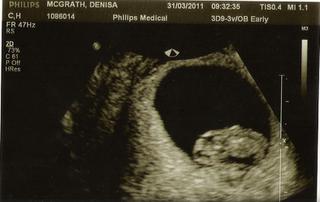

tak jen hlasim ze jsme v poradku, po chvilce hledani mi pani sonografka nasla nas druhy zazrak i s krasne blikajicim srdickem a meri jeste o den vic, tudiz ma 1,79cm to je co? 😀 ptala jsem se ji, aby se podivala jeste po druhem embryjku ale nic jineho nevidela, tak snad ted bude vse ok....u miusky jsem zacala prave krvacet po tom internim scanu ale to neznamena ze se to bude opakovat 😉 fakt se mi ulevilo 😵

a tady muj druhy zazrak 🙂